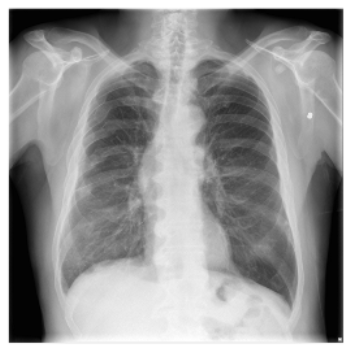

DatasetX-RayGenerated ReportGround Truth

Applsci 16 00470 i004Lung volumes are low. This results in crowding of the bronchovascular structures. There may be mild pulmonary vascular congestion.Lung volumes remain low. There are innumerable bilateral scattered small pulmonary nodules. Mild pulmonary vascular congestion is stable.